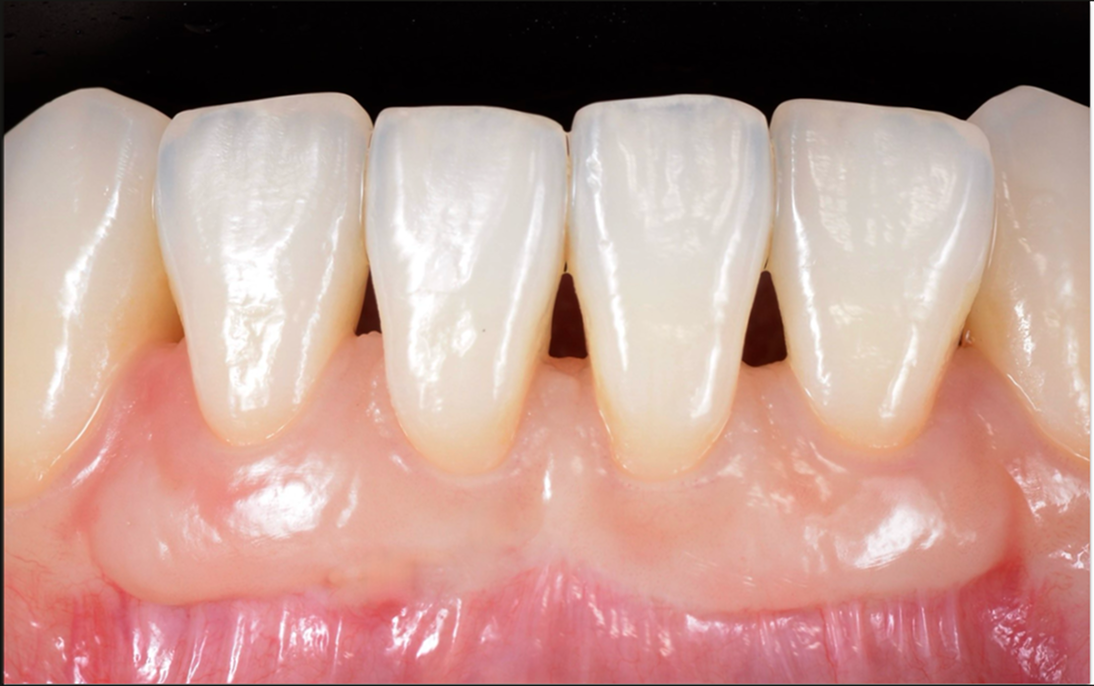

FGG(遊離歯肉移植術)

FGG(遊離歯肉移植術)とは、何らかの原因で角化歯肉(歯槽骨に付着する丈夫な角化層のある歯肉)が失われた箇所に、上顎の口蓋付近の採取しても問題のない部分からとった歯肉を上皮ごと移植する方法です。移植した歯肉が定着すると、見た目にも整った、機能的にも問題のない歯肉に回復します。